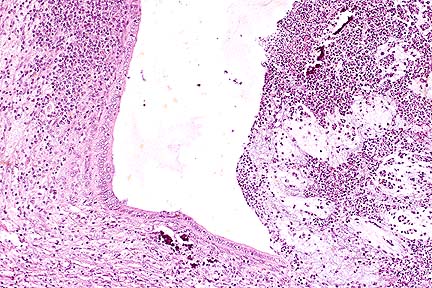

Necrotizing and suppurative rumenitis in a Hereford calf as a result of lactic acidosis. (HE, 40X, 84K)

Contributor's Diagnosis and Comments: Rumen: rumenitis, proliferative, vesiculopustular, diffuse, severe, bovine.

Microscopically, this rumen has epithelial hyperplasia and hyperkeratosis. The epithelium is edematous with vesicle formation, and a purulent inflammation is present with the formation of pustules. Large numbers of bacilli are on the lumenal surface along with a few yeast organisms consistent with Candida sp.

This lesion is typical of that produced in lactic acidosis due to grain overload. In this calf on a milk diet the lesion is caused by excessive milk entering the rumen and producing lactic acidosis. This can be caused by consumption of excessive amounts of milk, reticular groove dysfunction, or tube feeding of milk. The disease is not usually fatal but can result in weight loss and poor condition. This calf may have developed a secondary infection/septicemia which resulted in death.

AFIP Diagnosis: Rumen: Rumenitis, necrosuppurative, diffuse, moderate, with epithelial hyperplasia, and intracellular edema, Hereford, bovine.

Conference Note: The normal rumen is anaerobic with a pH of 6.5 and a microflora of gram-negative bacteria and protozoa that produce the volatile fatty acids; acetic acid, propionic acid, and butyric acid. Ingestion of easily fermentable carbohydrates causes an increase in total volatile fatty acids and lowers the rumen pH. As the pH drops, normal flora are replaced by Streptococcus bovis which produces lactic, formic, valeric, and succinic acids. At a pH less than 4.5, S. bovis is inhibited and there is an overgrowth of Lactobacillus, which produces large quantities of lactic acid, further reducing rumen pH. The rumen contains epithelial receptors that are activated by lactic, propionic, and butyric acid. Activation of these receptors cause a decrease in ruminal motility. The increase in volatile fatty acids also raises the osmotic pressure in the rumen, and there is movement of fluids from the vascular spaces into the rumen resulting in hemoconcentration, anuria, and hypotension. A systemic acidosis occurs as lactic acid is absorbed from the rumen. If the acidosis is uncompensated, death occurs due to decreased tissue perfusion, decreased cardiac output, and metabolic acidosis.

Histologic changes in ruminal acidosis are probably induced by the chemical environment and are characterized by vacuolation of epithelial cells (often leading to vesiculation), neutrophilic infiltration of the mucosa and submucosa, and mucosal erosions or ulceration.

Frequently, the damaged rumen is secondarily infected by Fusobacterium necrophorum or fungi. Other complications of rumenitis include laminitis and an encephalopathy which resembles polioencephalomalacia (this is probably caused by a decrease in thiamine producing bacteria).